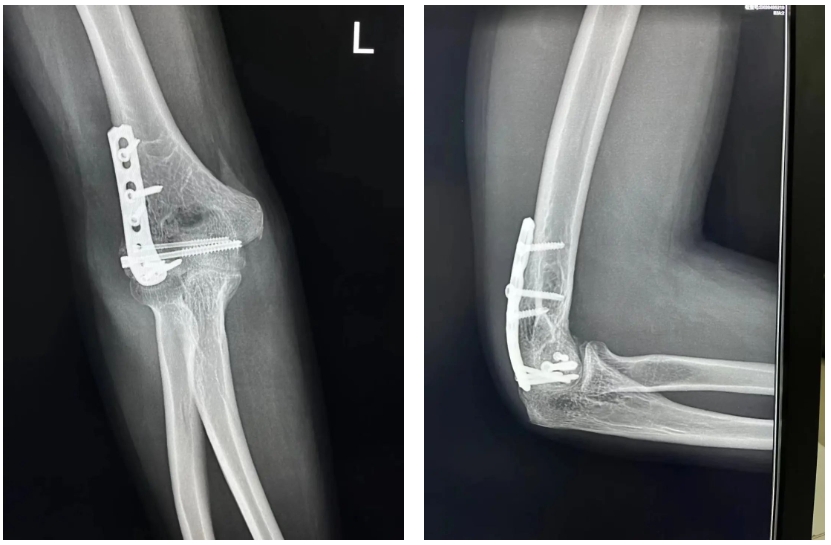

对外科医生而言,手就像生命一样宝贵。一旦其肘关节出现僵硬或残留不稳定,他将无法完成很多日常操作,更别提重回手术台、完成精细的腹腔镜手术。由于当地的医疗水平有限,小蔡很快想到曾经的老师和同事,就将自己的病史和影像资料传递给了瑞金医院骨科张胤医生。张胤医生的初步判断非常明确:肱骨远端粉碎性骨折的AO分型为1-3-B1型,冠状面暴力致外翻不稳定,需要手术治疗。瑞金医院运动医学中心主任王蕾仔细阅片和分析:肱骨滑车的外侧关节面有一块较大的压缩区域,这就引起了肱尺关节的不匹配。这块压缩区域相对独立,没有关节囊与其相连接,因此无法通过手法复位。更棘手的是,小蔡的肱骨小头粉碎骨折,结合肱骨滑车外侧关节面塌陷,导致他的肘关节外翻稳定结构受损,如不能及时手术恢复正常结构、早期功能锻炼,未来可能出现肘关节僵硬、慢性不稳定,乃至创伤性关节炎等并发症。他需要立即手术。

小蔡没有丝毫犹豫,当即订好机票,飞来上海。经过一系列充分的术前检查,在麻醉科姬梅副主任医师密切配合下,小蔡接受了肘关节切开复位植骨钢板内固定手术。术中,王蕾主任医师巧妙地利用肱骨小头的骨折线,做出了类似肱骨外髁截骨的入路,清晰暴露外侧肱尺关节面,翘剥复位关节面骨块,并植骨复位固定,既完美复位、坚强固定,又避免了创伤扩大。

骨折愈合摄片